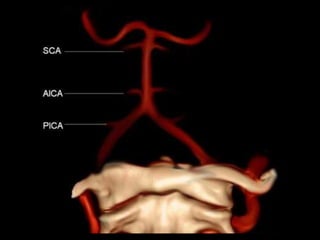

Basilar Artery

1 vertebral artery

2 (PICA)

3 basilar artery

4 (AICA)

5 (SCA)

5v vermian branch of SCA

5h hemispheric branch of SCA

6.1 P1 segment of (PCA)

6.2 P2 segment of (PCA)

-3D frontal view following vertebral

2 posterior inferior cerebellar artery

(PICA)

2v vermian branch of PICA

2h hemispheric branch of PICA

4 anterior inferior cerebellar artery

(AICA)

5 superior cerebellar artery (SCA)

6 posterior cerebral artery (PCA)

6.2 P2 segment of PCA

8 posterior temporal branch of PCA

9 parieto-occipital branch of PCA

10 calcarine branch of PCA

12 posterior thalamoperforating arteries

13L lateral posterior choroidal artery

16 pontine perforating artery